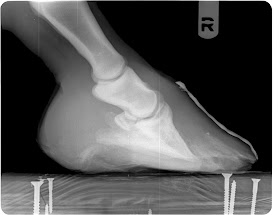

| Very first radiographs |

![]() |

| Good improvement in sole depth and new growth without fungal invasion |

| right front with 1/3 of new hoof growth. |